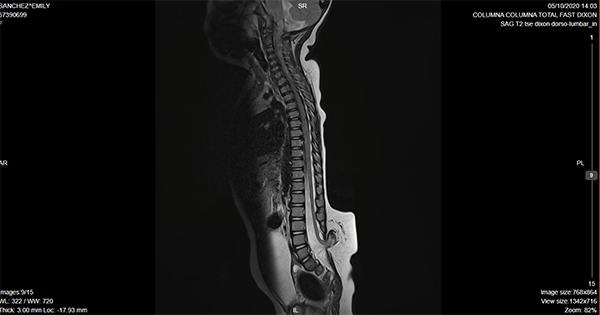

Caso ilustrativo n°3: Houkin tipo 3(Figura 3)

Paciente de 21 meses de vida, con diagnóstico de lipomielomeningocele lumbosacro, pie equinovaro bilateral. Urodinamia alterada con globo vesical asociado a pérdida de orina, cateterismo intermitente 3 veces/día. Potenciales evocados de miembros inferiores con alteración de la vía somestésica. Se realizó cirugía de desanclaje medular. Paciente permaneció en decúbito ventral 12 días con peso en herida. Posteriormente presentó colección de LCR en colgajo a los 7 días. La cual no fistulizó ni requirió punciones. Se manejó con tratamiento conservador y evolucionó favorablemente. Alta a los 14 días de la cirugía.

Se consideró Houkin tipo 3 por ser esperable, ya que la colección de LCR en este tipo de cirugías es muy frecuente, más allá del cierre hermético de la duramadre.

Figura 3: Imagen por Resonancia Magnética de columna lumbosacra donde se evidencia disrafismo lumbar, compatible con lipomielomeningocele.